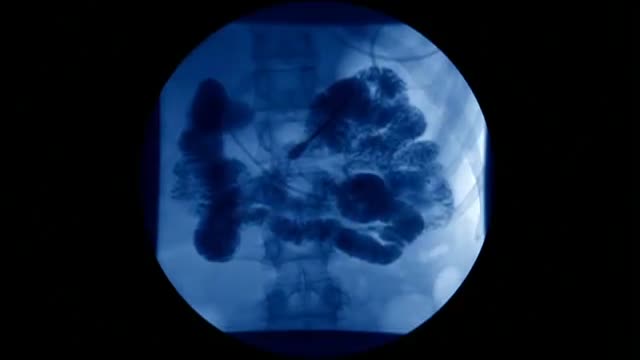

Living Well With Ulcerative Colitis

Being diagnosed with ulcerative colitis doesn’t have to stop you from doing the activities you love. Former professional Canadian athletes share their inspiring stories of living well with ulcerative colitis.